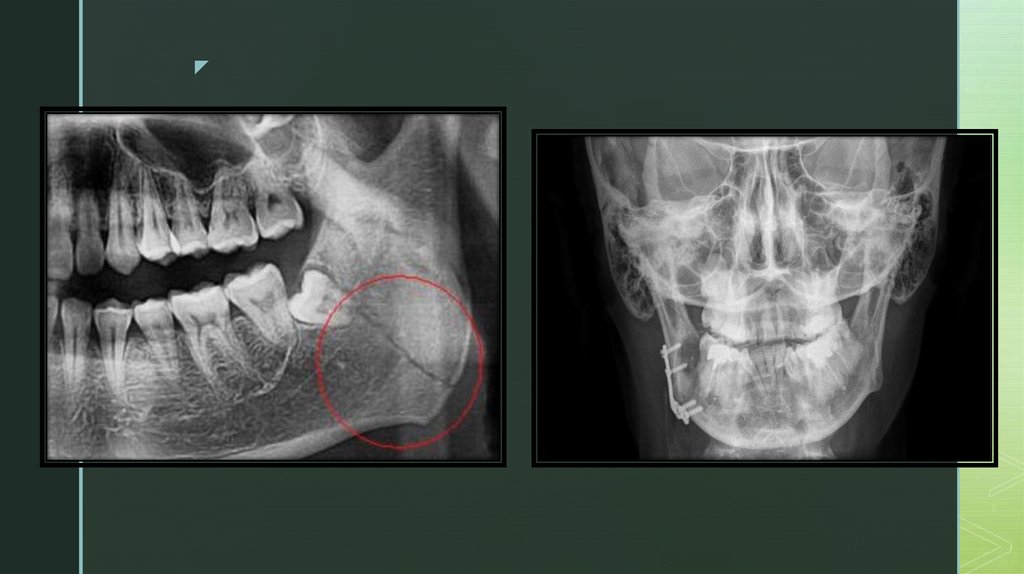

Диагностика

При пальпации нижней челюсти выявляется костный выступ, дефект кости или

болезненная точка, чаще в области наиболее выраженной припухлости мягких

тканей или гематомы.